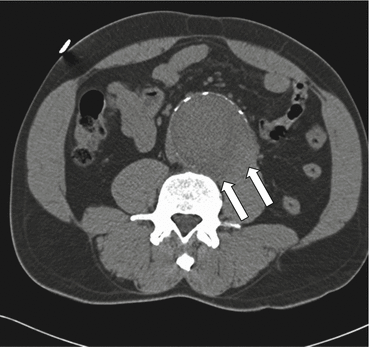

Fig. 7.3

Draped aorta sign. Precontrast transaxial CT shows abnormal contour of the aortic lumen and loss of the fat plane between the aorta and the left psoas muscle (arrows), the “draped aorta” sign in an aneurysm with contained rupture